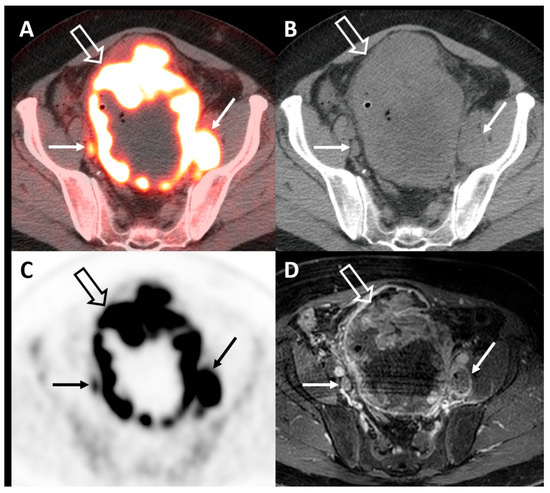

5.2. FDG-PET/CT for Bladder Cancer Staging

5.3. FDG-PET/CT for Neoadjuvant Chemotherapy Response and Restaging

5.4. Alternative PET Tracers in Molecular Imaging of Bladder Cancer

5.5. PET/MRI in Bladder Cancer